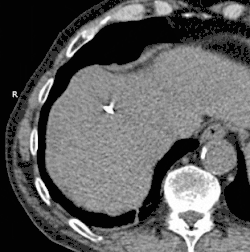

![]() Animated GIF showing cryoablation of mass in right liver lobe using two probes. Time elapsed is approximately 30 minutes. | |

Cryoablation is a process that uses extreme cold to destroy tissue. Cryoablation is performed using hollow needles (cryoprobes) through which cooled, thermally conductive fluids are circulated. Cryoprobes are positioned adjacent to the target in such a way that the freezing process will destroy the diseased tissue. Once the probes are in place, the attached cryogenic freezing unit removes heat from ("cools") the tip of the probe and by extension from the surrounding tissues.

The most common application of cryoablation is to ablate solid tumors found in the lung, liver, breast, kidney and prostate. The use in prostate and renal cryoablation are the most common. Although sometimes applied in cryosurgery through laparoscopic or open surgical approaches, most often cryoablation is performed percutaneously (through the skin and into the target tissue containing the tumor) by a medical specialist, such as an interventional radiologist. The term is from cryo- + ablation.